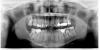

Force Опубликовано 2 октября, 2011 Поделиться Опубликовано 2 октября, 2011 Какой порядок лечения правильный в моем случае? Сколько времени, приблизительно, может занять выравнивание нижнего ряда в моем возрасте? Мне 56 лет Заранее благодарю К сожалению не могу выложить все необходимые фото, т.к. нахожусь на лечении не в моем городе, нет фотокамеры с собой Кратко, дисфункция ВНЧС, как правильно отметил Скип, требует соответствующих знаний от доктора. Перво наперво - перелечить каналы - там у вас хаос. Потом заниматься прикусом и выравниванием челюсти в пространстве и зубов после диагностики и определения терапевтической позиции с помощью шины (каппы, сплинта и т.д.) Ссылка на комментарий